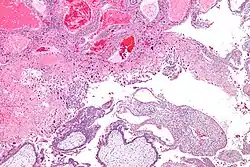

| Micrograph of intermediate trophoblast and a hydatidiform mole (bottom of image). H&E stain. | |